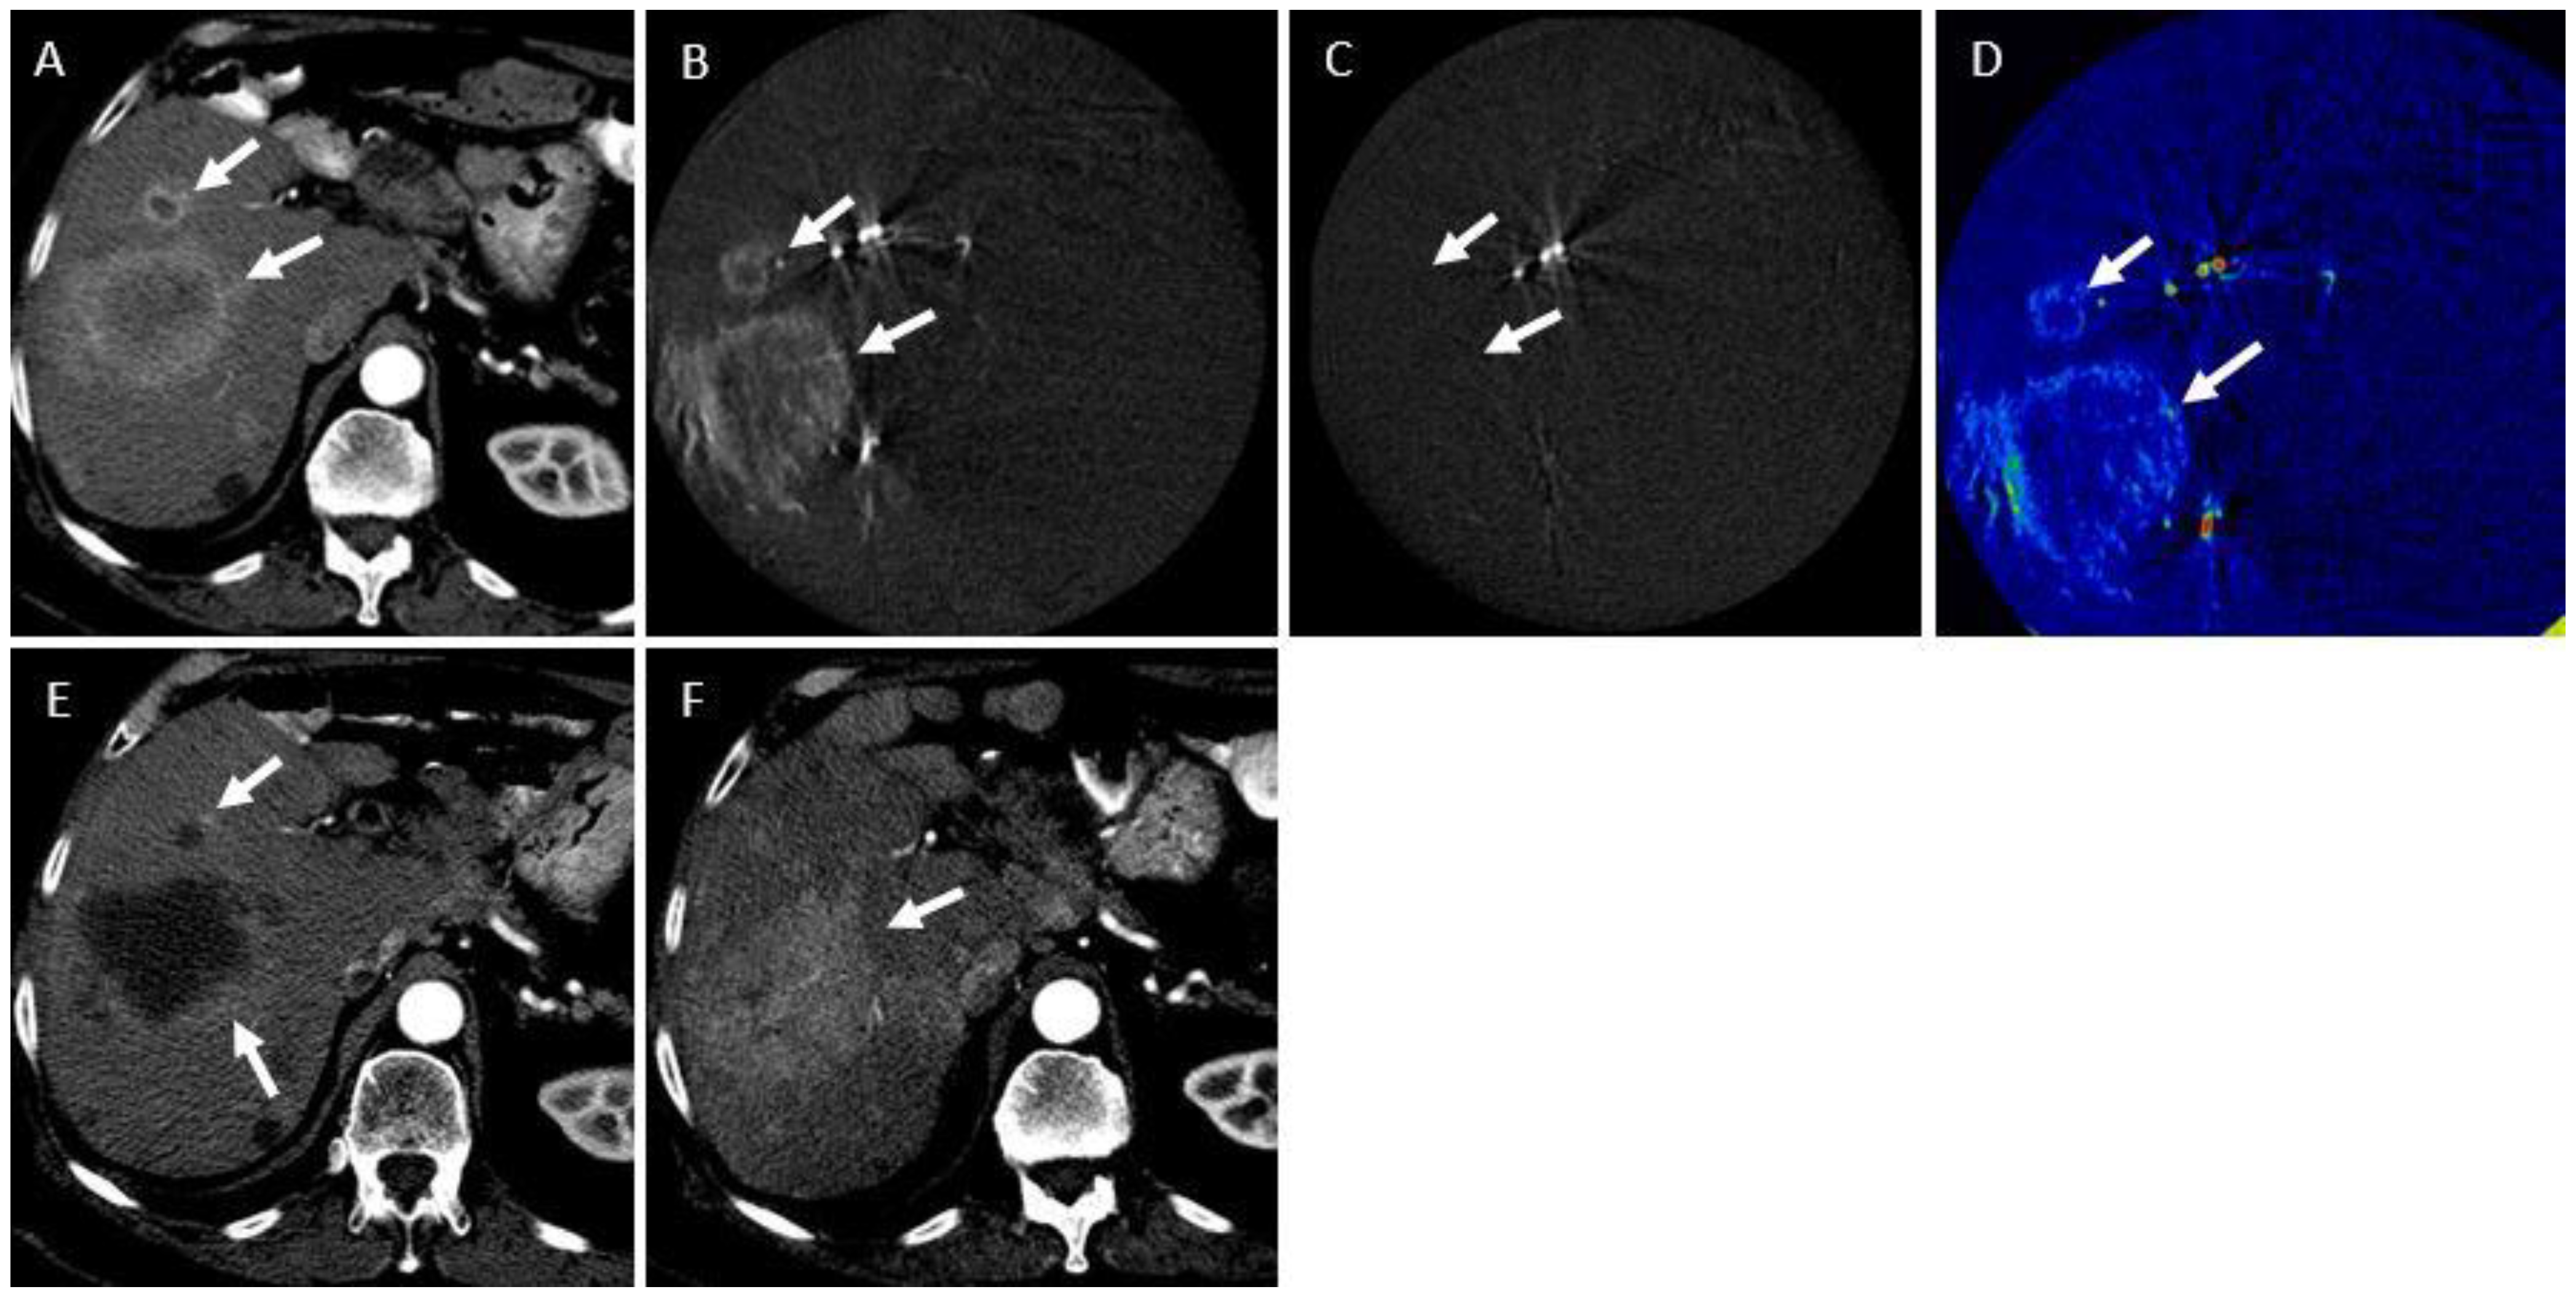

2.3. CBCT Acquisition and Contrast Injection

2.4. Calculation of Tumor Enhancement Parameters

2.5. Assessment of Treatment Response